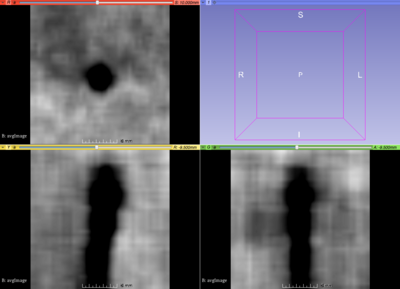

- Tip detection : We wrote a script using SimpleITK to extract and re-sample all the tip regions from images using needles from manual segmentation. These 115 cubical regions can now be used for data analysis (machine learning). As a first step, we built an average model (template) of the needle tips to be matched to new data sets, e.g. using convolution/correlation filters:

Example of artifacts from needle tips in MRI

Average intensity model from 115 needle tips

Our hypothesis that the needle tip artifact show out in the average needle tip model could not be confirmed at this time: We need to use more cases with needle tip artifacts (instead of mixing with other cases from other MR sequences). Secondly, we should sort out the needle tips from the obturator needles.

Third, the little cubic image around the needle tip could be registered to each other before averaging to fit more accurately. For now, the origin is registered, but the orientation could be improved. After convolution (SimpleITK) the average needle tip model with a patient MR image, this approach suffers from over-segmentation.